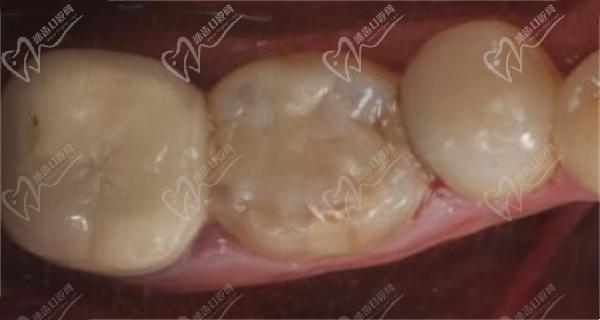

2】牙齿修复:对于较重的牛牙症,可以考虑使用牙齿修复方法,如烤瓷冠或全瓷冠来改变牙齿的形状和大小。这些方法通常需要将牙齿磨小并覆盖上人造冠,以改善牙齿的外观和功能。

3】牙齿美容:对于极重度的牛牙症,可能需要进行牙齿美容来改善牙齿外观。这包括使用美容修复技术,如贴面或全冠美容修复,以改善牙齿的颜色、形状和大小。

牙冠修复